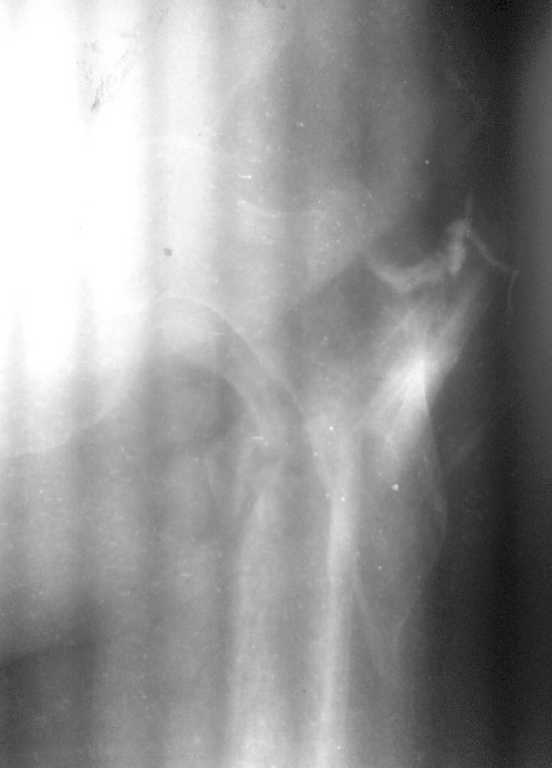

Фистула функционирует от случая к случаю - последние 2 дня выделений небыло, сделали контрастирование (с трудом вошло 5 мл контраста). Признаков воспаления в зоне поражения нет, лабораторные показатели в пределах нормы. Судя по распростарнению контраста - локальный остеомиелит в месте расположения стержня АВФ

План следующий: 1.контрастирование зелёнкой, ФНСЭ, дренирование+бусы с антибиотиком

2. если нет распространеия контраста в область грушевидной ямки и места перелома - БИОС стержнем с цементным покрытием

3. если распространение в указаные области есть - дренирование, бусы, заживелние раны, дистракция отломков, БИОС